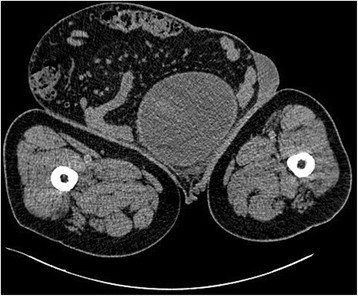

แต่ผล CT Scan แสดงให้เห็นว่า เนื้องอกขนาดใหญ่ราว 30 เซนติเมตรนี้ แท้จริงแล้วคืออาการจากโรคไส้เลื่อนที่ขาหนีบ ซึ่งเกิดขึ้นหลังจากลำไส้เล็กของคนไข้ได้เคลื่อนตัวออกจากบริเวณอุ้งเชิงกราน จนทำให้ลูกอัณฑะของเขาถูกกดทับและบวมเป่งจากภายใน

โดยในรายงานระบุว่า คณะแพทย์ได้ผ่าตัดเปิดผิวหนังออกมา และพบว่าภายในถุงอัณฑะที่บวมเป่งนั้นมีทั้งลำไส้เล็ก บางส่วนของลำไส้ใหญ่ และของเสียอีกจำนวนหนึ่ง

ภาพจาก Journal Case Reports